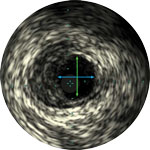

Lumen with fresh thrombus

Micro-calcification

Calcified plaque with acoustic shadowing

Vessel size: 6 mm diameter Plaque morphology: Mixed, thrombic plaque with medial calcium Plaque geometry: Eccentric lesion Guidewire position: True lumen

Quick-Cross catheter: Confidently cross challenging morphologies Turbo-Power laser atherectomy: Forward facing directional debulking to clear thrombus; rotation for improved deliverability in calcified lesions AngioSculpt scoring balloon: Safely dilate residual stenosis4 Stellarex DCB: Designed for performance in calcium